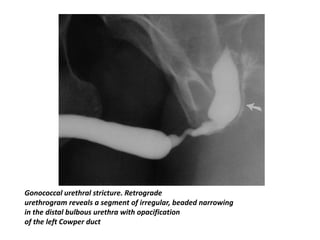

• The typical urethrographic finding in gonococcal urethral stricture is

an irregular urethral narrowing several centimeters long.

• While the bulbar urethra is the most common area of occurrence,

gonorrheal strictures may occur anywhere in the anterior urethra or

Gonococcal urethral stricture. Retrograde

urethrogram reveals a segment of irregular, beaded narrowing

in the distal bulbous urethra with opacification

of the left Cowper duct